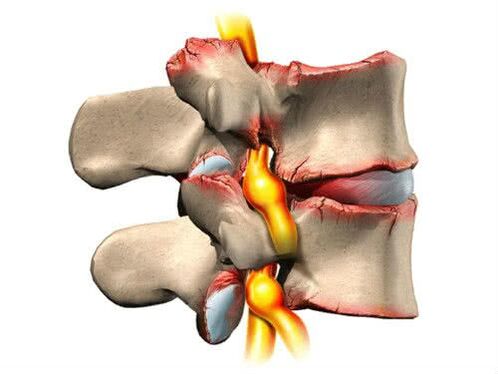

Osteochondróza je klasifikovaná v štádiách, berúc do úvahy klinické príznaky, stupeň poškodenia tkaniva a úroveň nepohodlia pacienta. Patologický proces prebieha v štyroch fázach:

- Predklinické. Najprv sa znižuje základná úroveň výživy medzistavcových platničiek, zhoršuje sa ich elasticita a pevnosť. Na röntgene nie je možné zistiť žiadne zmeny. Pacient môže pociťovať miernu únavu, mierne nepohodlie, stuhnutosť, závrat, bolesť hlavy;

- Štádium diskogénnej radikulitídy. Vláknitý krúžok sa začína pomaly deformovať (objavujú sa trhliny a výčnelky). Bolesť sa stáva ostrejšou a náhlejšou, nepohodlie sa stáva zreteľnejším. Objaví sa príznak ako „lumbago“, končatiny začnú byť znecitlivené;

- Cievne-radikulárne štádium. Fibrinózny prsteň úplne stráca svoj tvar. Od tohto momentu sa môžu vytvárať kýly. Röntgenové lúče sú veľmi informatívne. Subjektívne pocity pacientov sú výrazné (bolesť, ostré záchvaty bolesti, neustále nepohodlie). Objavujú sa časté svalové kŕče a výkon prudko klesá. Ak nervové vlákna trpia, potom sú prvé príznaky dysfunkcie vnútorných systémov nevyhnutné;

- Keď sa výška stavcov znižuje, začína medzi nimi trenie. Ako kompenzačný mechanizmus sa môžu objaviť osteofyty. Ide o špecifické osteovýrastky, ktoré pomáhajú posilniť oblasť, kde bolo trenie najintenzívnejšie. Ale osteofyty môžu vyvolať zápalové procesy v okolitých mäkkých tkanivách, čo zhoršuje patologický obraz.